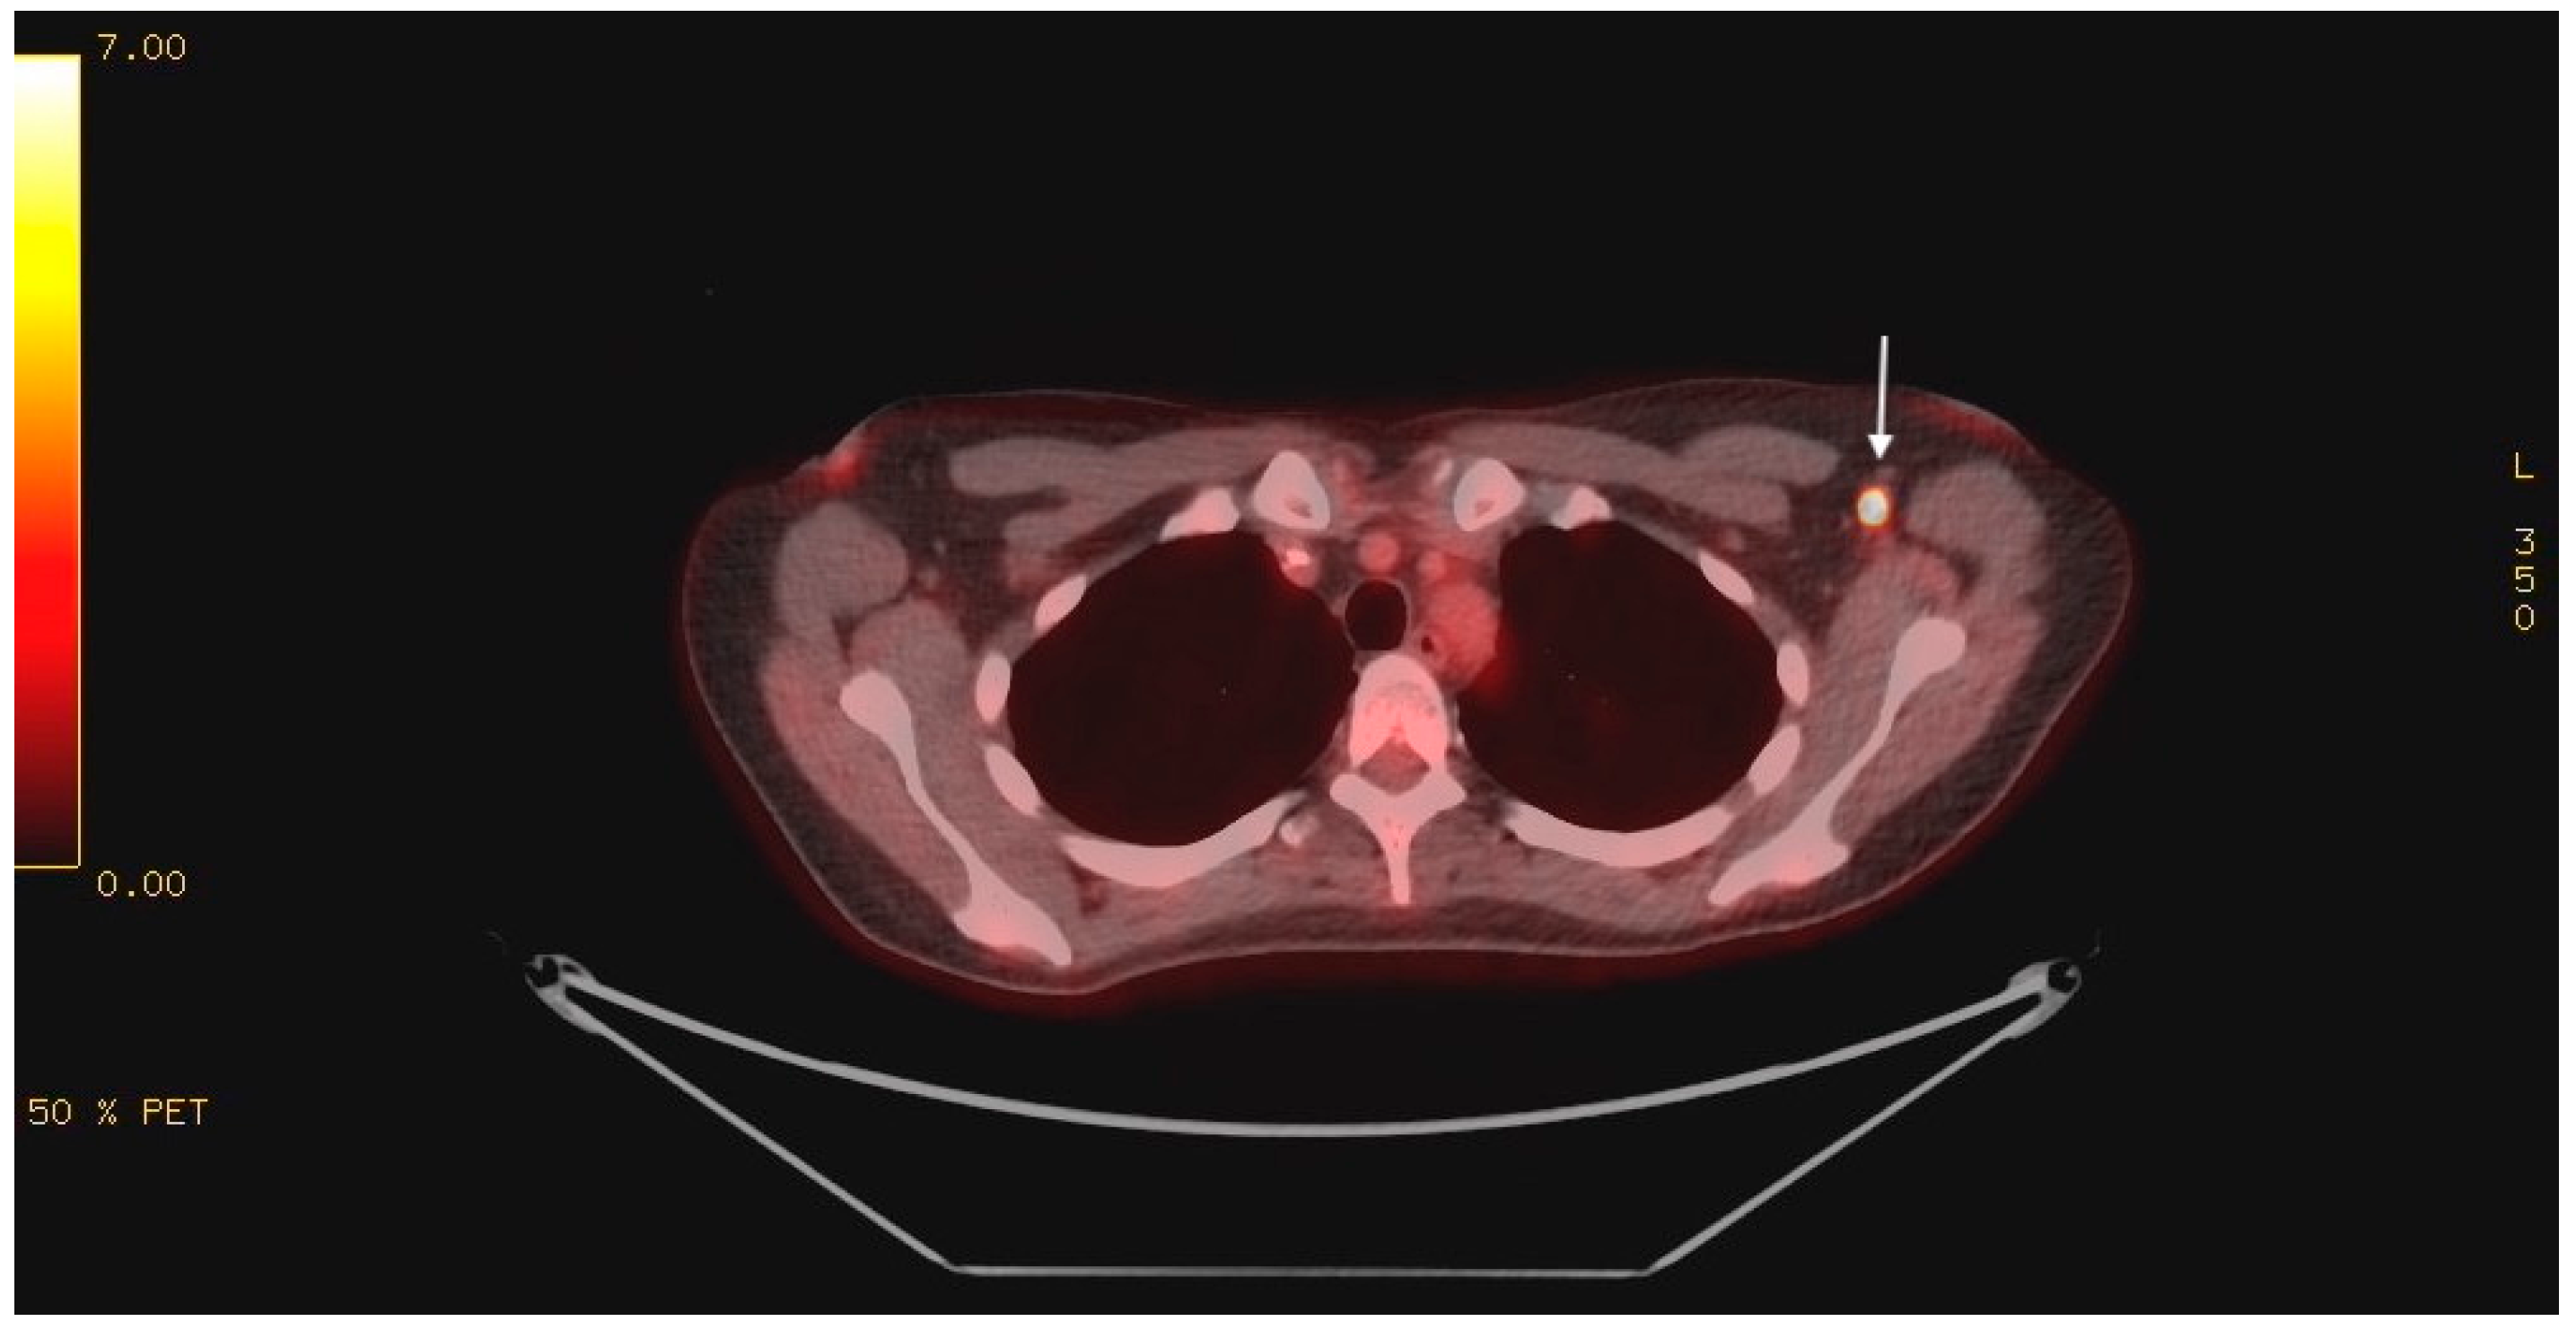

Magnetic resonance imaging (MRI) of the brain with gadolinium showed no evidence of acute cerebral ischemia, intracranial hemorrhage, encephalitis (including cerebellitis), mass, or evidence of leptomeningeal disease. Cerebrospinal fluid (CSF) analysis showed a normal cell count, protein, glucose, negative testing for a comprehensive viral PCR panel, negative bacterial cultures, and no evidence of malignant cells on cytology. Given the MRI brain and CSF findings, infectious and post-infectious etiologies became less likely, and a paraneoplastic investigation ensued. Paraneoplastic panel in serum was negative for the following autoantibodies: myositis-related antigen, Hu (ANNA-1), Yo, Ri (NOVA-1), PNMA2 (Ma2Ta), Ampiphysin, CV2.1, Recoverin, SOX1, Titin, GAD65, Zic4, and Tr. Tumor markers, including CEA, CA19-9, AFP, beta-hCG, CA-125, and CA15-3, were all within normal limits. CTs of the chest, abdomen, and pelvis were unremarkable. Pelvic ultrasound ruled out a gynecologic malignancy. The patient underwent a positron emission tomography (PET) scan, which revealed intense 18-FDG uptake in a solitary, 7 mm left axillary lymph node with a maximum standard unit value (SUV Max) of 19.0 (Figure 1). No other findings of concern were identified.

Figure 1.

PET scan showing intense 18-FDG uptake in the left axilla (indicated by white arrow).